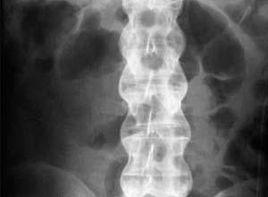

骶髂關節炎是強直性脊柱炎的病理標誌,也常是其最早的病理表現之一。骶髂關節炎的早期病理變化包括軟骨下肉芽組織形成,組織學上可見滑膜增生和淋巴樣細胞及漿細胞聚集、淋巴樣濾泡形成以及含有IgG、IgA和IgM的漿細胞。骨骼的侵蝕和軟骨的破壞隨之發生,然後逐漸被退變的纖維軟骨替代,最終發生骨性強直。脊柱的最初損害是椎間盤纖維環和椎骨邊緣連線處的肉芽組織形成。纖維環外層可能最終被骨替代,形成韌帶骨贅,進一步發展將形成X線所見的竹節樣脊柱。脊柱的其他損傷包括瀰漫性骨質疏鬆、鄰近椎間盤邊緣的椎體破壞、椎體方形變及椎間盤硬化。其他脊柱關節病也可觀察到相似的中軸關節病理學改變。

(1)骶髂關節炎多數病人首先出現骶髂關節受累症狀,個別病人也可首先出現較高位脊柱關節炎症狀,表現為下背部強直和疼痛,常放射到一側或兩側臀部,偶爾放射到大腿,進一步可發展至膝關節背側,甚至可擴展至膝關節以下。由於骶髂關節局部炎症,下肢伸直抬高征一般都呈陰性。直接按壓病變關節或使患側下肢伸直,可誘發疼痛。在病程早期就可出現下背部運動受限和輕度骶髂關節椎旁肌痙攣。用手指按壓恥骨聯合、髂骨嵴、坐骨結節也可誘發疼痛。骶髂關節受累呈對稱性,恥骨聯合也可受累。病人可固定為某一姿勢(圖2,3)。